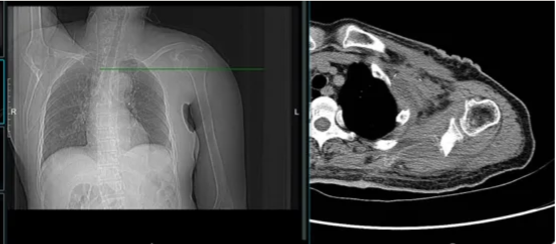

图示:手术采取前后联合入路

图示:左图前入路分离前方血管神经与肿瘤,右图示腋窝切口保护腋动脉(黄色箭头)及外侧索、后侧索神经(红色箭头)

图示:后方入路切除肿瘤组织,软组织巨大缺损,利用LARS韧带将残余的斜方肌、菱形肌与残余肩胛骨缝合(黄箭头),重建肩关节